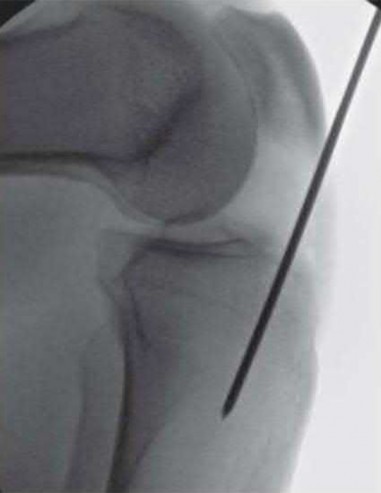

Question 1:

A 12-year-old obese boy presents with vague left thigh and knee pain. He is diagnosed with a Slipped Capital Femoral Epiphysis (SCFE) as seen in similar clinical scenarios. During percutaneous in-situ fixation, unrecognized penetration of the guide wire into the hip joint occurs. What is the most likely specific complication resulting from this technical error?

Correct Answer: Chondrolysis

Explanation:

Chondrolysis is a severe complication of SCFE characterized by rapid destruction of the articular cartilage. While it can occur idiopathically, its most established iatrogenic cause is unrecognized intra-articular hardware penetration. The 'approach-withdraw' fluoroscopic technique is required during pinning to assure pins are entirely intraosseous. Avascular necrosis (AVN) is usually due to damage to the epiphyseal blood supply (retinacular vessels) secondary to the initial displacement, forceful closed reduction, or posterosuperior pin placement.